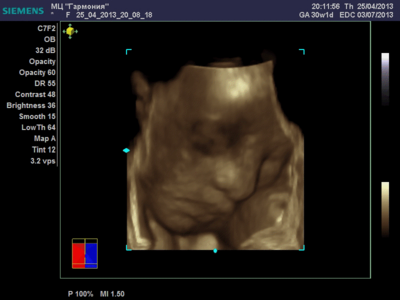

Ксюнь, а мы вообще не поняли. Она на всех фотках разная, да еще размытость такая. Пуповина то на носу болталась, то руками-ногами закрывалась. Главное что четкости нет совсем. Лоб у мужа тоже большой, а носы и губы зачастую на 3Д-4Д выходят разамазанно-пухло-приплюснутыми Поставлю для наглядности фотку моей средней-Джианки с 3Д УЗИ, там видно черты намного лучше и она на себя ту похожа сейчас, хотя родилась мне совсем на фото УЗИ не казалась похожей.

| Вложения: |

KENZEL,OLESYA_3.JPG [ 56.84 КБ | Просмотров: 1426 ]

katerina73 писал(а): Вот, пожалуй, самая лучшая фотография. Катюш, так ваш пупсик зато отлично виден, черты лица отменно видны. Те первые две вчерашние, вторые средней дочки. Со средней черты отлично видны, с этой куклой не понятно..

Катюш, какой прикольный бутузик ! Олесь, после фотки средней - точно прям похожи!

Олеся ну красотка у тебя!! слушай еще один губастик будет  по моему ты зря, очен прилично лицо видно девочки у всех такие сладкие они на этих фотках